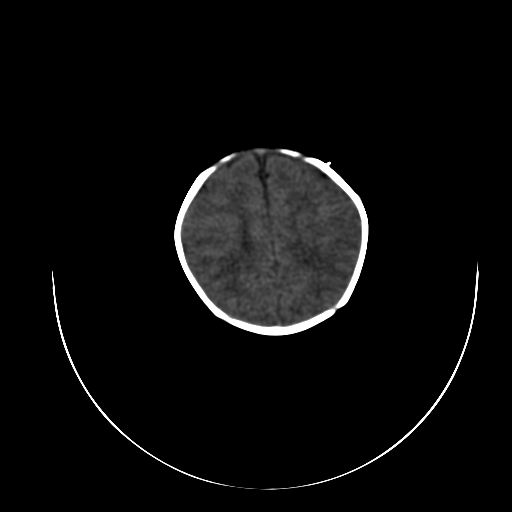

标题: PED0840:女,1.6岁,全身粘膜黄染6天,医生考虑新生儿胆红素 [打印本页]

标题: PED0840:女,1.6岁,全身粘膜黄染6天,医生考虑新生儿胆红素

正常  机器伪影

双侧脑实质多发低密度灶;是图象燥声?烟雾病?         右基底节到顶叶高密度灶,长轴大于宽度,伪影?出血灶??

机器伪影,每层都有,如果是病灶那不成了园柱形的了吗

每层都有且没有改变,应该是机器伪影。

谢谢拉,经过第二次扫描,就没有看见了,

开始我们也怀疑是机器伪影,但又怕是其他的。

不敢下结论。